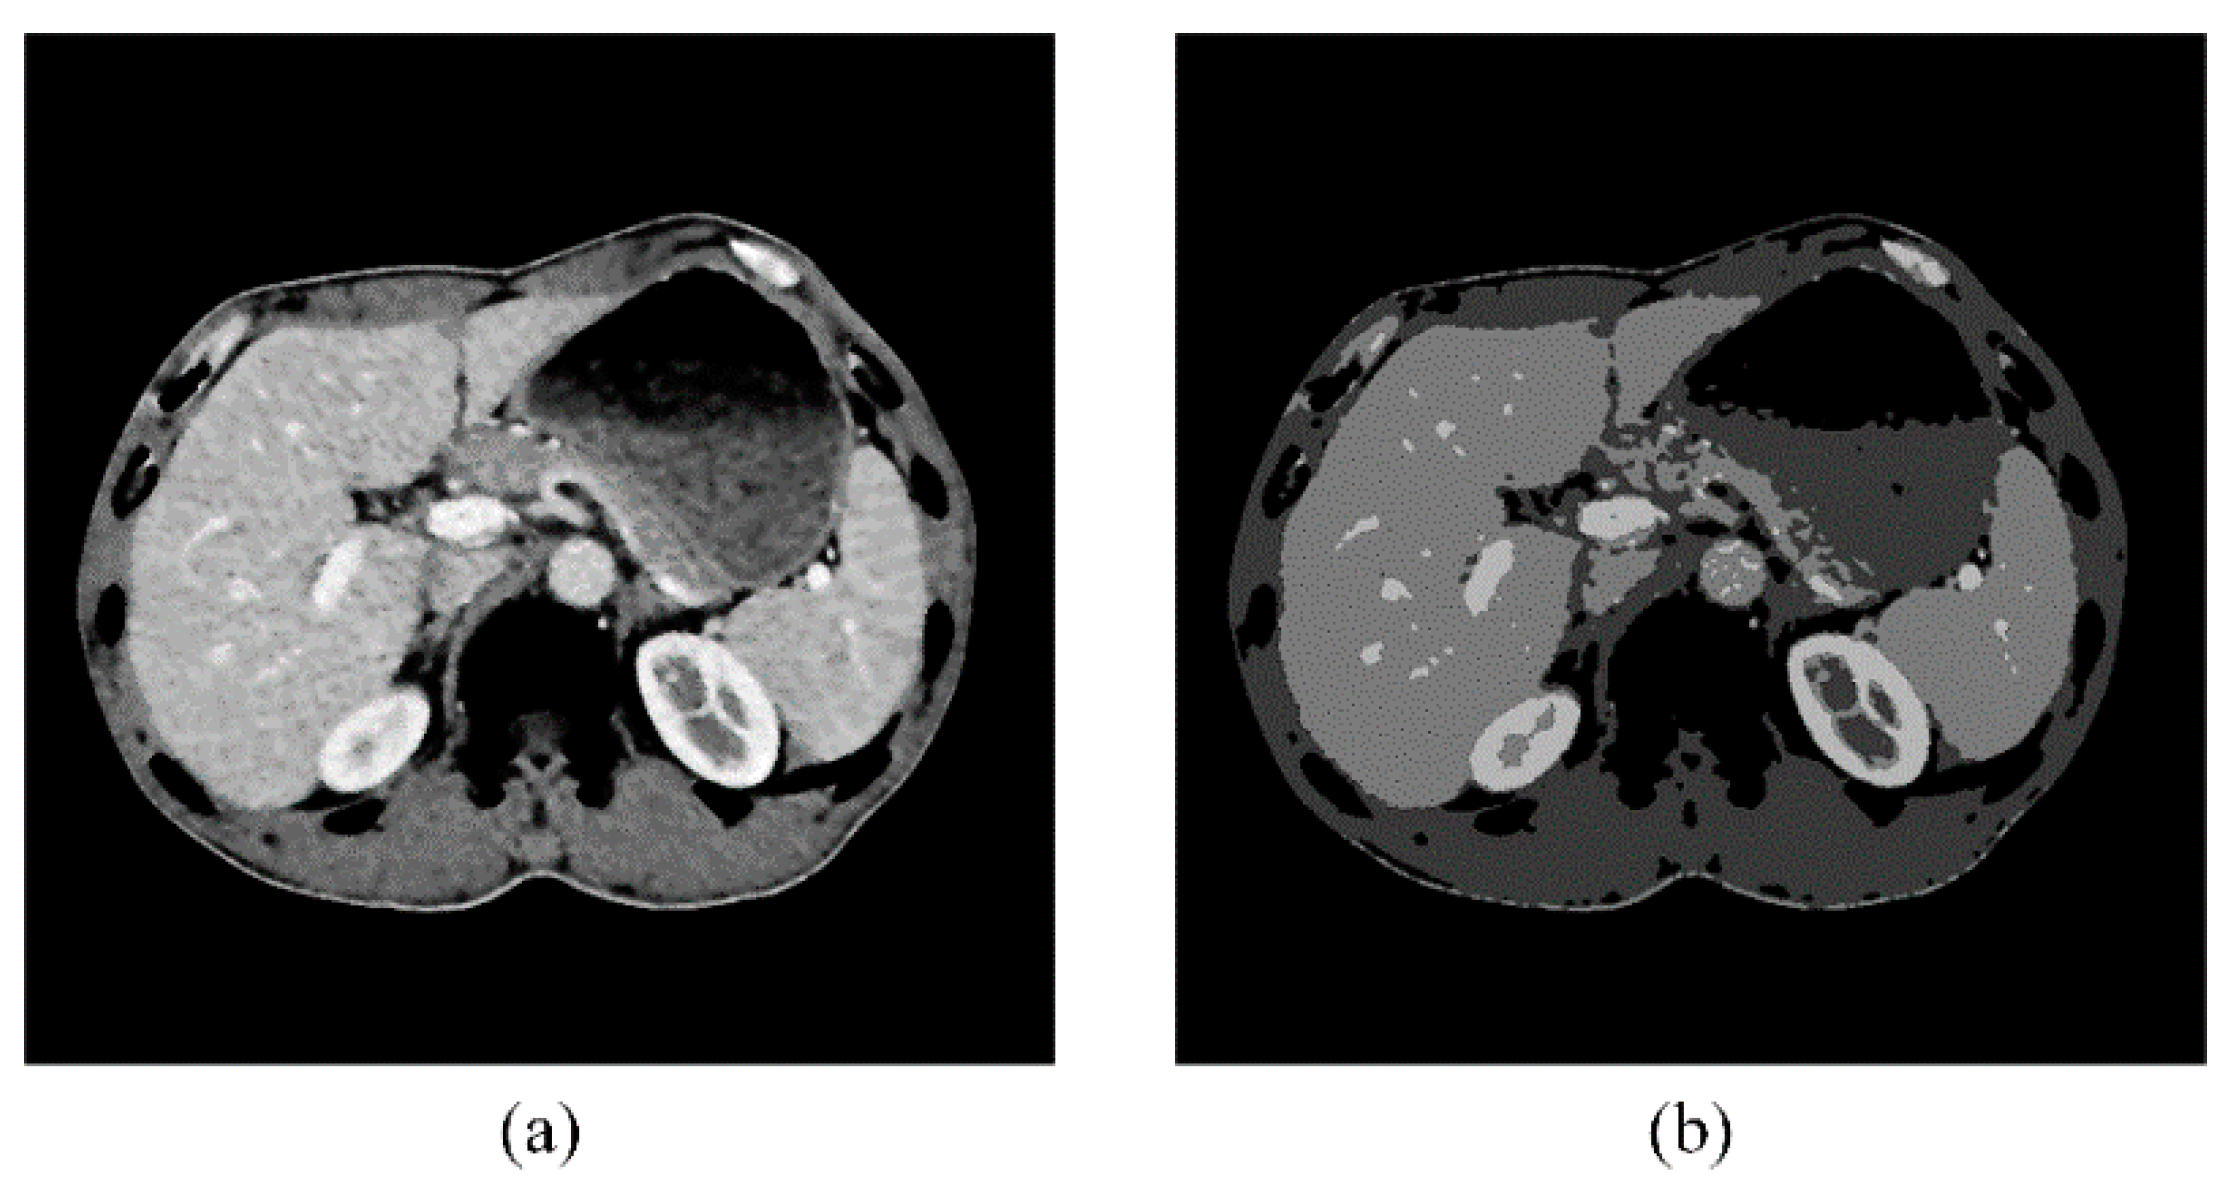

The GCBAC algorithm is efficient but struggles to evolve its contour to the concave areas of the target object. In Figure 11a, the green contour represents the initial contour, and the narrow band is the area between the two red contours. In Figure 11b, the blue contour represents the improved GCBAC segmentation result, while Figure 11c shows the manual segmentation result by experts. It is evident that the curve failed to evolve to the indentation of the kidney, primarily composed of adipose tissue. To address this issue, we incorporate postprocessing to the GCBAC result using the multi-regions volume histogram algorithm. Adipose tissue is low density and will cluster to the class with the smallest clustering center value. Therefore, removing this class from the GCBAC algorithm’s outcome will yield better results.

Figure 11. The evolution of GCBAC algorithm. (a) Initial contour is marked in green with its narrow band between red contours. (b) Modified GCBAC algorithm segmentation result is marked in blue. (c) Manual segmentation by experts is marked in red.